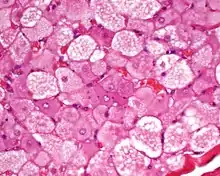

The tumors histologically resemble brown fat. There are four histologic types recognized, but one is the most frequently seen (typical). There is a background of rich vascularity.

- Lobular type: Variable degrees of differentiation of uniform, round to oval cells with granular eosinophilic cells with prominent borders, alternating with coarsely multivacuolated fat cells (pale cells). There are usually small centrally placed nuclei without pleomorphism. The cells have large cytoplasmic lipid droplets interspersed throughout.[4][5]

Hibernoma (intermediate magnification).